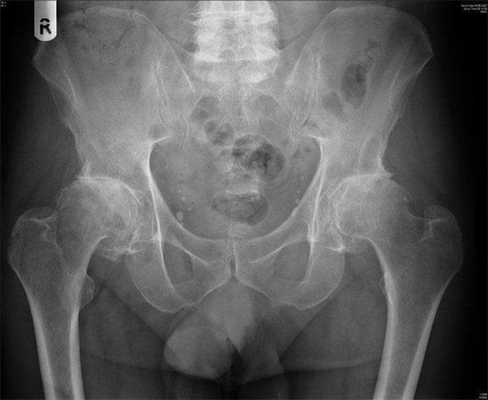

Двухсторонний коксартроз, обратите внимание на симметричное отсутствие суставной щели обоих суставов.

Отметим, жидкое протезирование не лечит суставы. Если кто-то все еще надеется на чудодейственное исцеление необратимых изменений посредством внутрисуставных инъекций, раскроем секрет, он попросту теряет деньги и время. Хрящ уже не восстановится, если имеется коксартроз 3 степени, и уколы здесь делать бессмысленно.